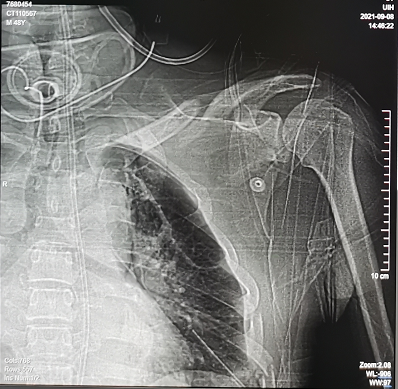

2021年8月19日,杨先生不慎从工地高处坠落,被紧急送至当地医院,入院后行头胸CT检查,提示右侧额颞顶脑挫伤伴硬膜下出血,蛛网膜下腔出血,枕骨骨折,左锁骨骨折,左肩胛骨骨折,左侧多肋骨骨折,胸椎横突骨折。因病情危重,在经过一系列抢救后,被送入了ICU病房。

入院诊断:颅内损伤  硬膜外血肿 脑术后 颅骨缺损 肺部感染 枕骨骨折 左锁骨骨折  左肩胛骨骨折 左多肋骨骨折 胸椎横突骨折 头皮裂伤 心包积液 胸腔积液 脂肪肝

手术前